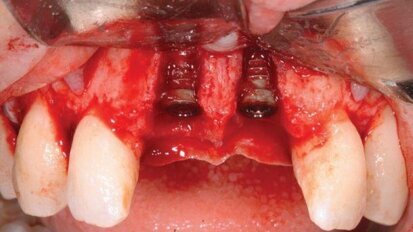

Regeneracja kości i pokrycie recesji w leczeniu estetyczno-implantologicznym

Autor prezentuje opis przypadku leczenia kompleksowego z planowaniem w centralnej relacji. Wykonano zabieg przeszczepienia pełnego bloku kostnego i ...

Odbudowa ubytku kostnego w szczęce allogennym blokiem kostnym z PRP

W pracy przedstawiono przypadek pacjentki z defektem kostnym w odcinku przednim szczęki powstałym po zabiegu ekstrakcji zęba 11, połączonym z ...